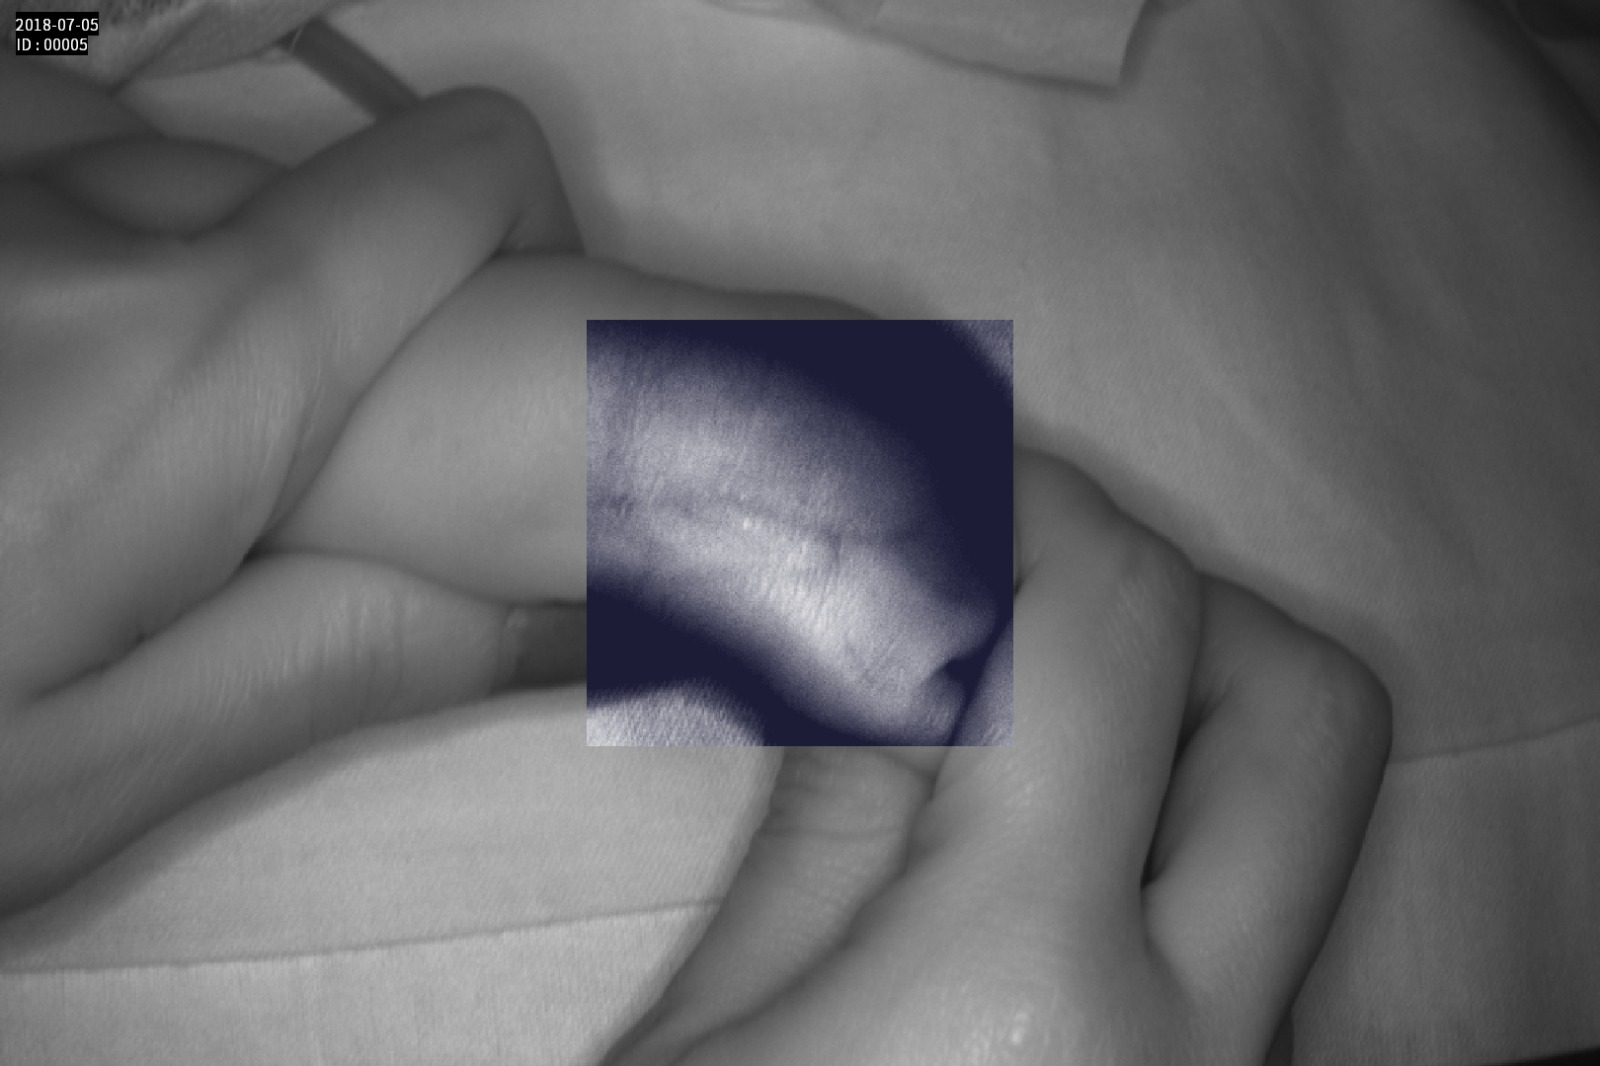

Dispozitiv medical portabil, non-contact, ce ajută la vizualizarea venelor pentru efectuarea puncției venoase, intervențiilor chirurgicale plastice, diagnosticul venelor varicoase.

Grad mare de detecție a venelor greu vizibile până la 10 mm adâncime (inclusiv vene faciale)

Imaginea venelor este proiectată pe monitorul propriu în timp real si ajută la identificarea corectă și precisă

Multiple aplicații de vizualizare vene atât la sugari cât și la pacienții obezi sau în urgențe indiferent de tonul de culoare a pielii